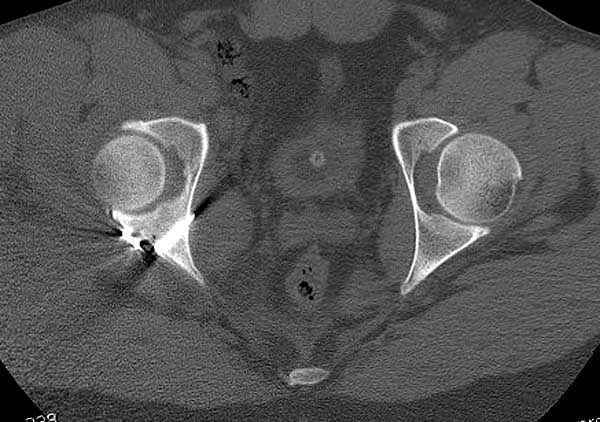

11:50 больной в послеоперационной, рентгенограмма N7, компьютерная томограмма в тот же день N8-10

На рисунке N1 предоперационный план лечения ложного сустава шейки бедра- линия ложного сустава, угол и направление введения импланта, клиновидная остеотомия в градусах и миллиметрах, второй снимок после коррекции, расчет, на сколько удлиняется конечность и размеры импланта;

N3 рисунок окончательный снимок, после операции моя рентгенограмма должен выглядеть примерно как эта картина. На N4 снимке клин перед удалением; N5 послеоперации 3 нед.; N6 окончательная рентгенограмма.

варус при проксимальном отделе 95 градусной пластиной.

Интересно бы посмотреть рентгенограмму таза (оба сустава) а также рентгенгорамму с захватом коленных суставов (по Dror Paley).